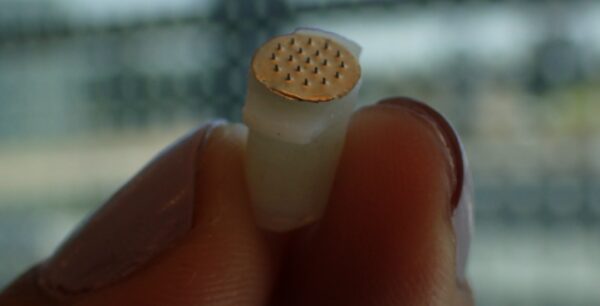

Αμερικανοί ερευνητές παρουσίασαν ένα νέο πειραματικό φάρμακο που δημιουργεί ελπίδες ότι κάποτε θα μπορούσε να χρησιμοποιηθεί κατά της νόσου Αλτσχάιμερ, καθώς παρουσιάζει ενθαρρυντικά αποτελέσματα σε πειράματα που έκαναν σε ποντίκια. Σύμφωνα με στοιχεία που παρουσίασαν στο ετήσιο συνέδριο της Αμερικανικής Εταιρείας Αναισθησιολογίας ο καθηγητής Αναισθησιολογίας Μοχάμεντ Ναγκίμπ και οι συνεργάτες του στην Κλινική του Κλίβελαντ, […]